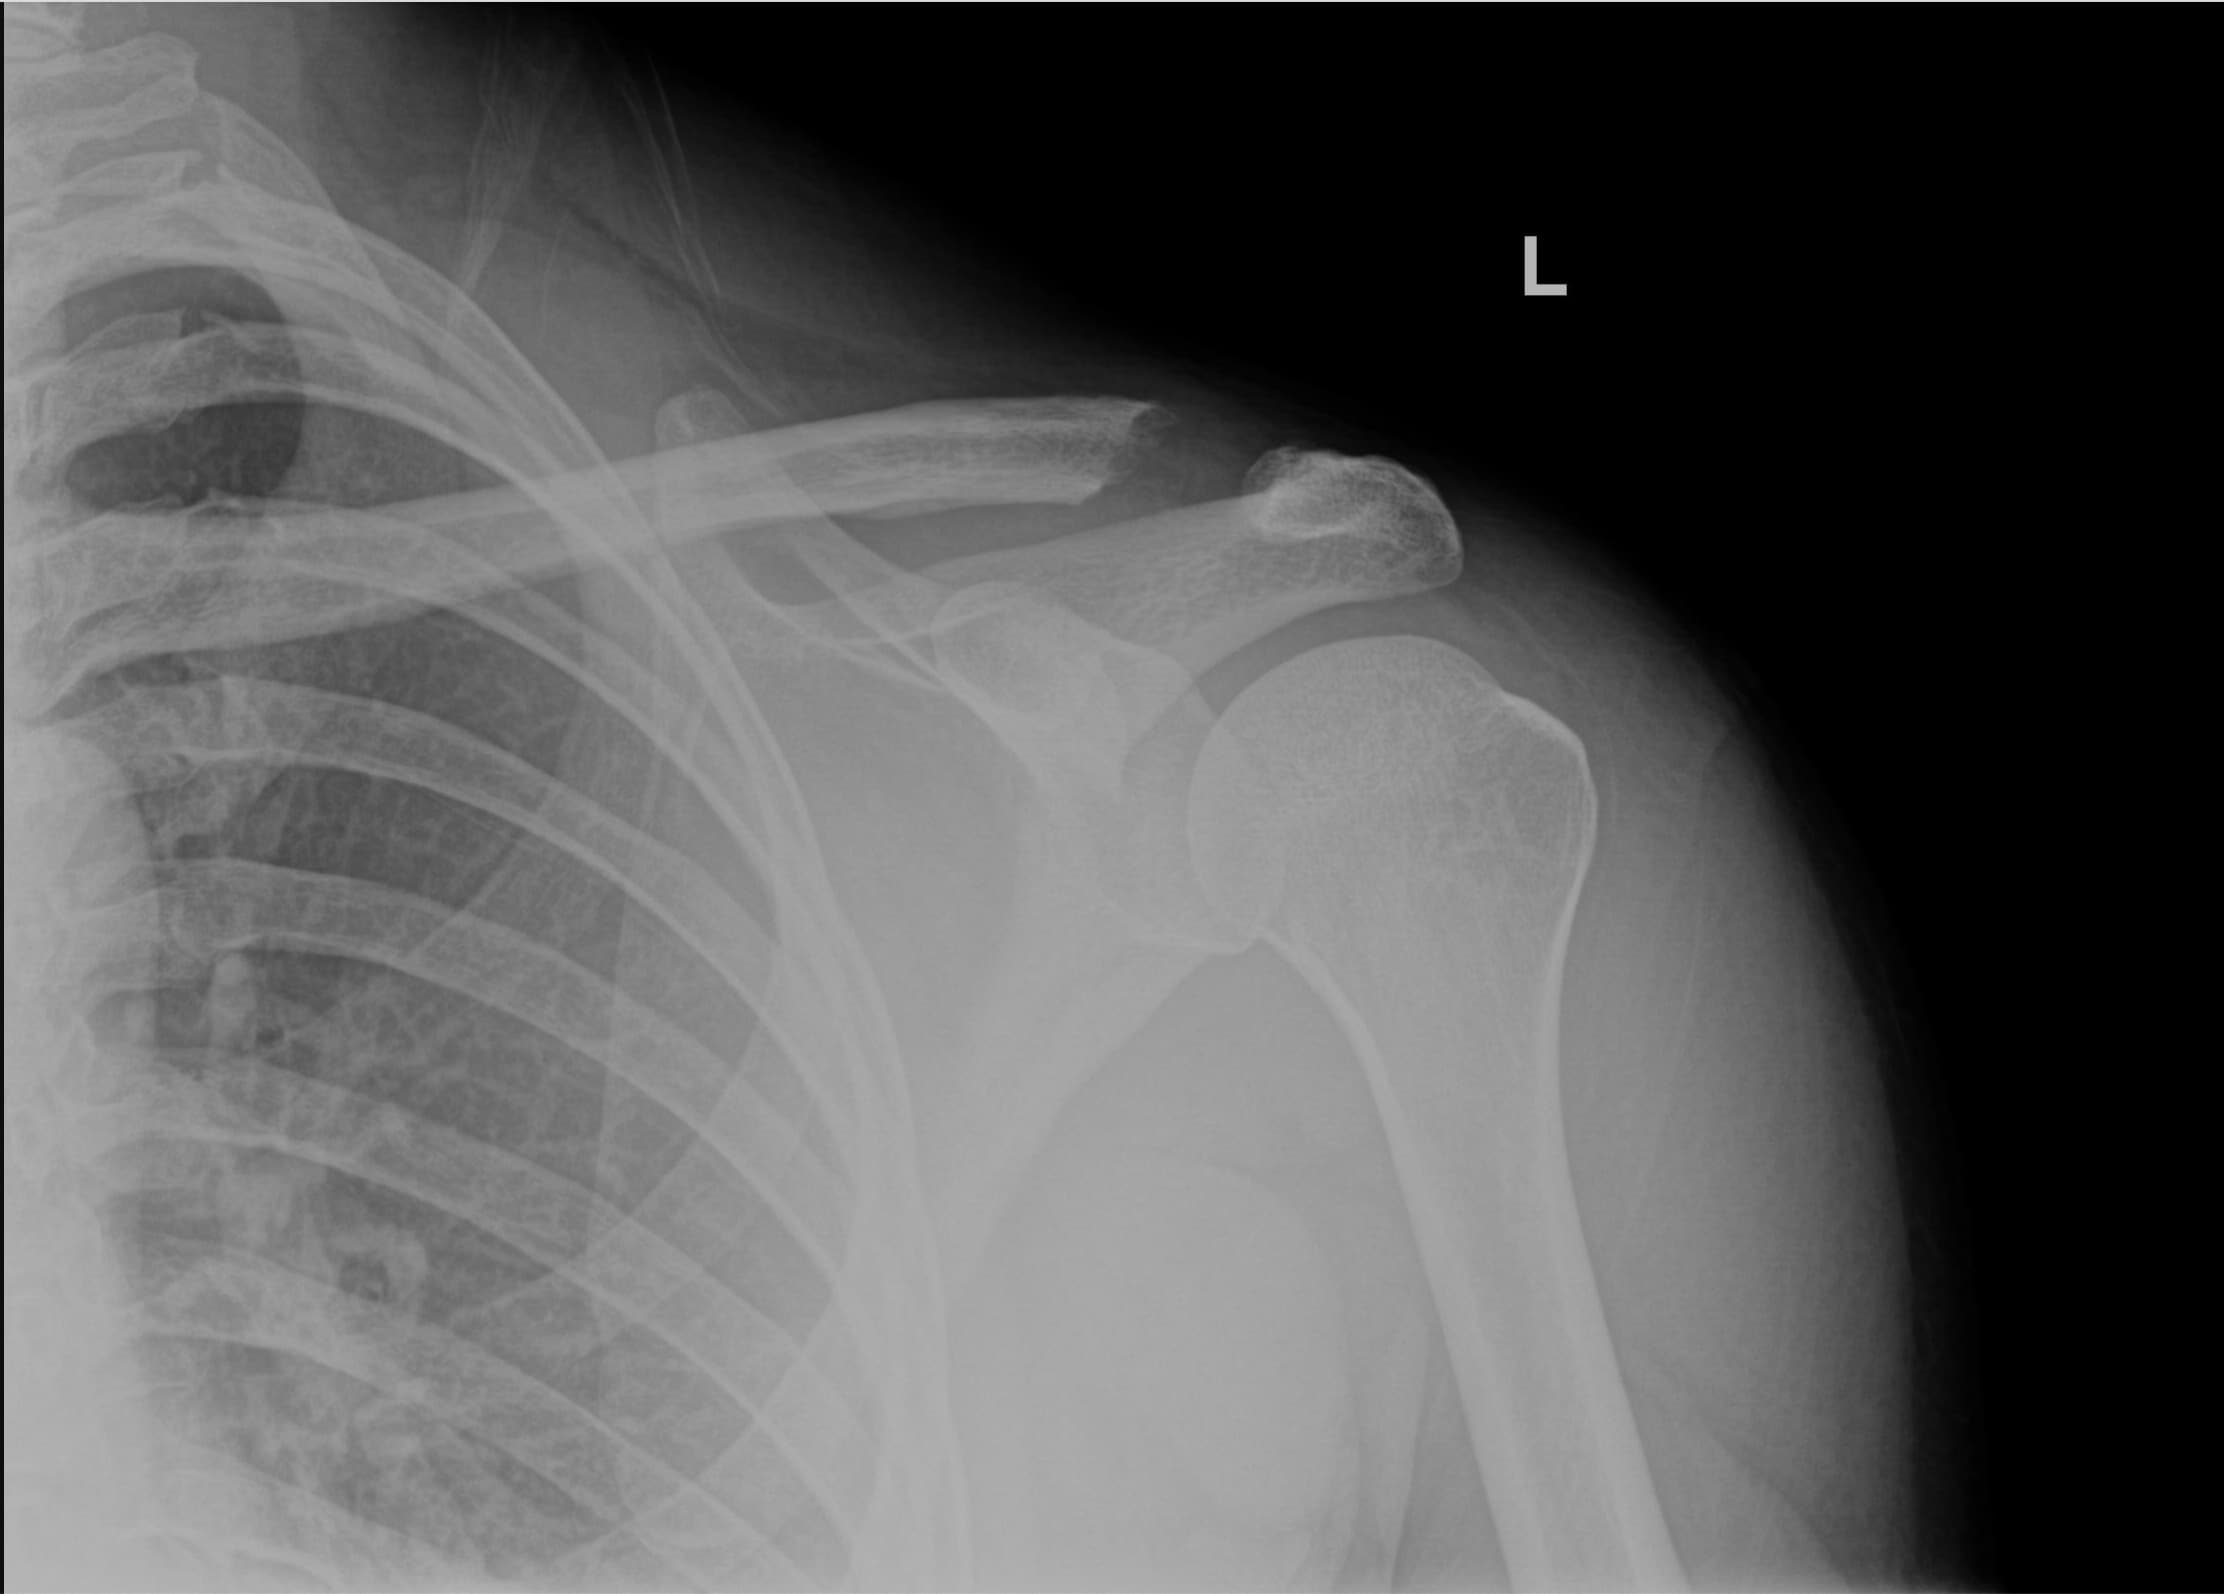

Post-Operative X-RAY of patient clavicle